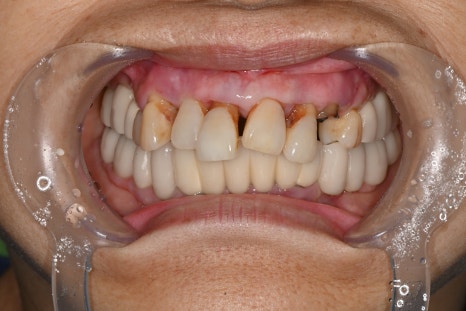

심미를 결정하는 보철 디자인

전치부 임플란트에서 가장 중요한 단계는

보철 디자인입니다.

이번 케이스에서도

맞춤형 어버트먼트 적용

임시 보철을 통한 형태 확인

최종 지르코니아 보철 제작

과정을 거쳐 완성되었습니다.

앞니는 단순히 하얀 치아가 아니라

✔ 자연스러운 색상

✔ 빛이 통과하는 투명도

✔ 잇몸과의 경계

가 모두 자연스러워야 합니다.

치료 후 변화

치료 후 환자분은을 경험하셨습니다. 특히

“내 치아처럼 자연스럽다”는 반응을 보이셨습니다.

자연스러운 앞니 회복

미소 개선

발음 안정

식사 기능 회복